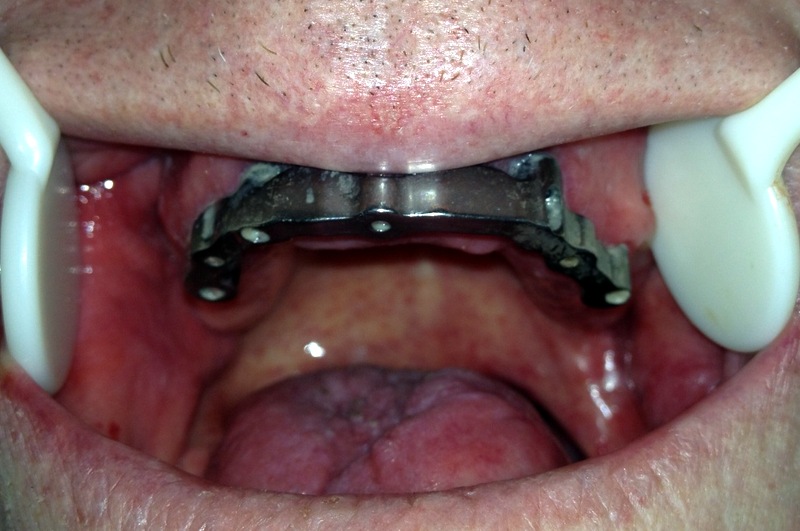

A Lower Implant Frame To Support A Denture

A Upper Implant Frame To Support A Denture